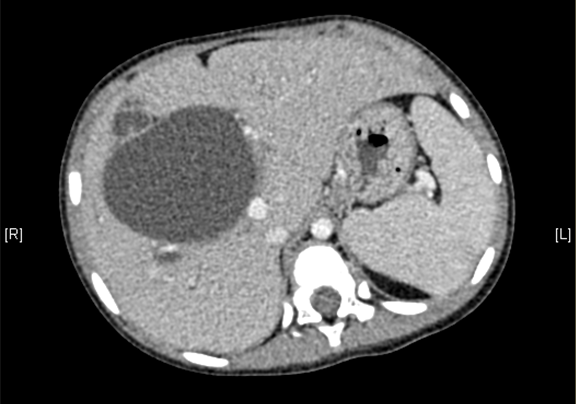

术前CT检查:

平衡期

上腹部增强CT:考虑先天性胆管扩张症(胆总管明显)。

将0.625mm双源薄层CT资料的静脉期和动脉期Dicom格式文件导入海信CAS系统。

通过调节窗宽窗位调整CT序号,对肝实质,胆囊,胆总管,下腔静脉,肝动脉、门静脉及肝静脉等进行三维重建;系统自动计算肝脏体积。